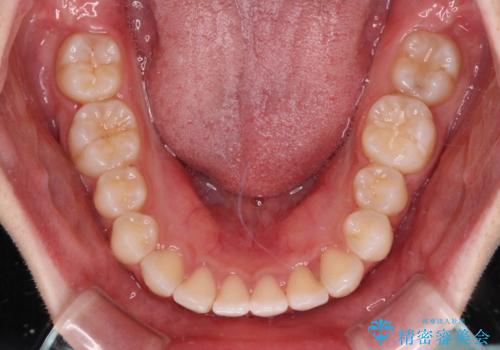

インビザライン特有の、奥歯の咬み合わせの問題もなく、しっかりと歯列を改善することができました。

舌側転位している上顎側切歯(内側に引っ込んでいる真ん中から2番目の歯)は、インビザラインが最も移動を苦手とする歯であり、これ以上の改善を望まれる場合にはワイヤー矯正、あるいはワイヤー矯正の併用をお勧めいたします。